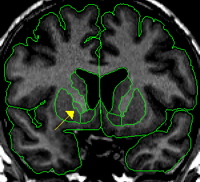

| General Description  In the coronal view the pallidum resembles a rounded triangle that continues off the putamen. The pallidum starts anteriorly as a small triangle and reaches its largest extent in its most medial slices and then dwindles to a small triangle again in the most posterior slices. The pallidum is essentially surrounded by white matter except for the lateral border which is the putamen. The putamen and pallidum are separated at this border by a thin strip of white matter called the lateral medullary lamina. Medially, pallidum is difficult to discern from the surrounding white matter because although it is gray, in terms of its intensity, its darkness is frequently fainter than putamen.  Procedure | |